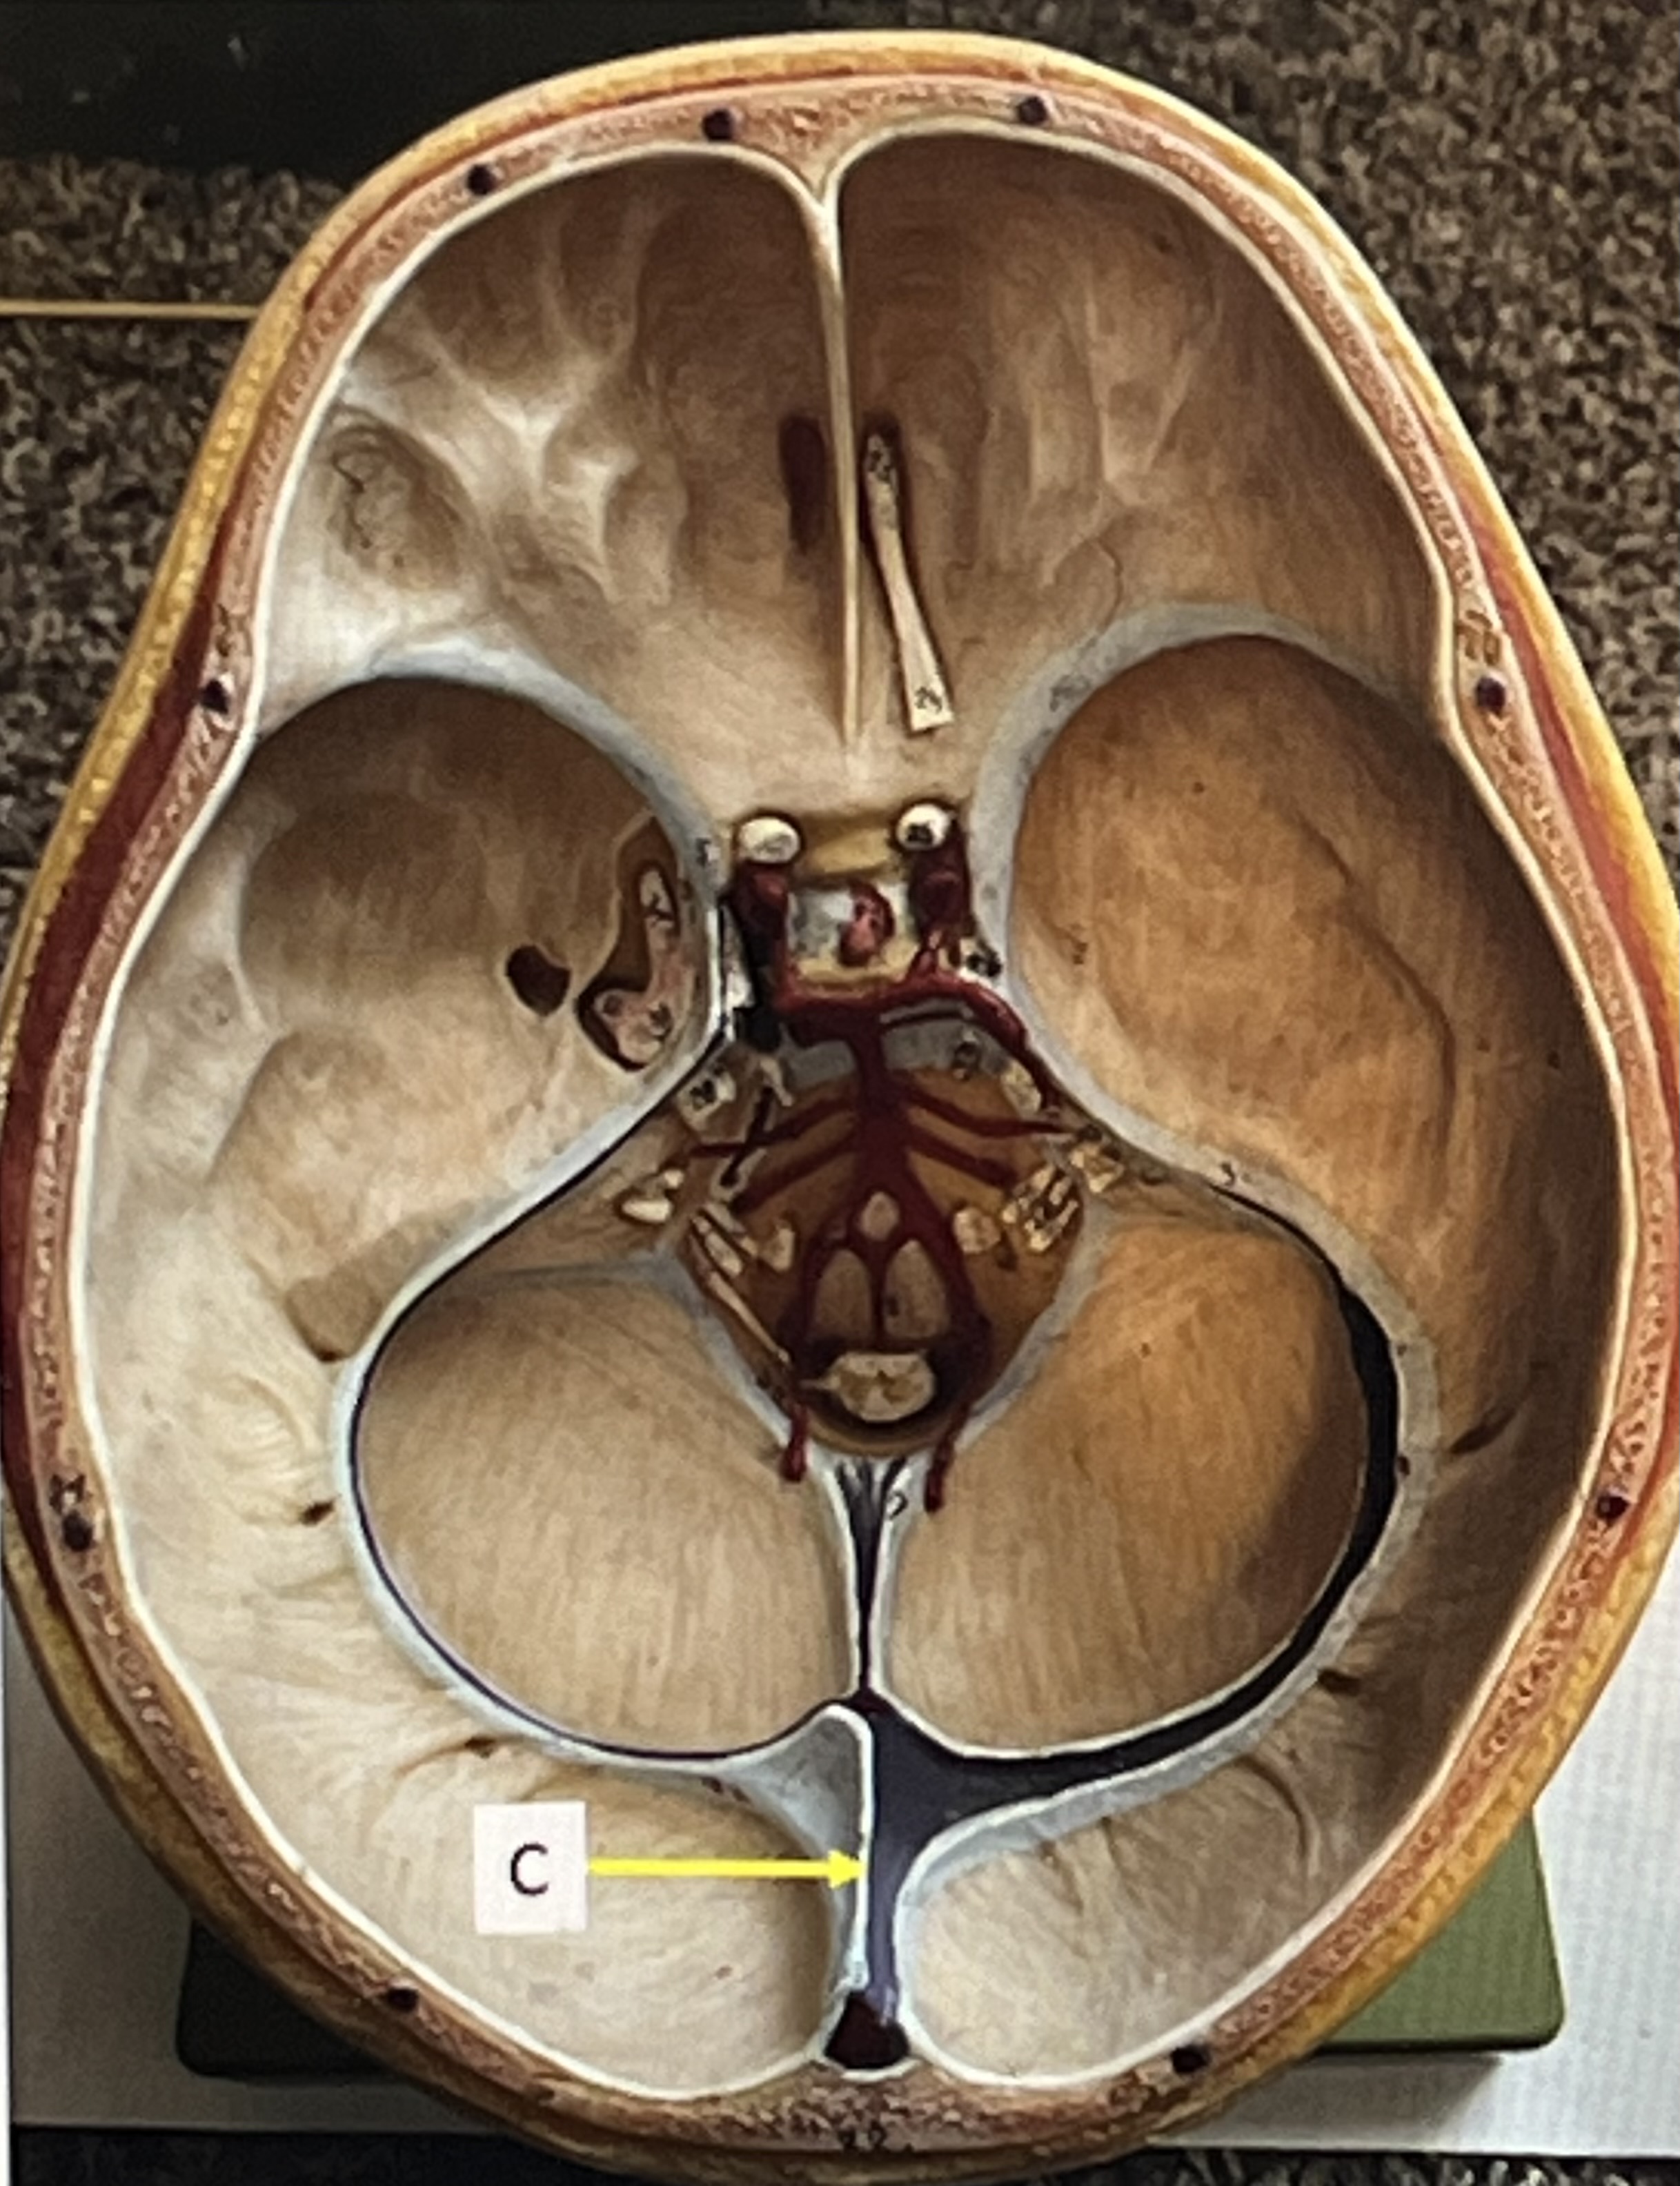

dura mater folds: falx cerebri

dura mater folds: falx cerebelli

dura mater folds: tentorium cerebelli

What is C?

3rd ventricle